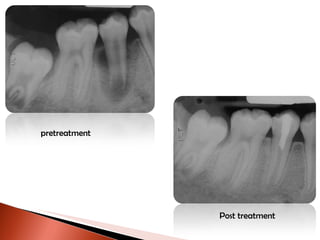

pretreatment Post treatment